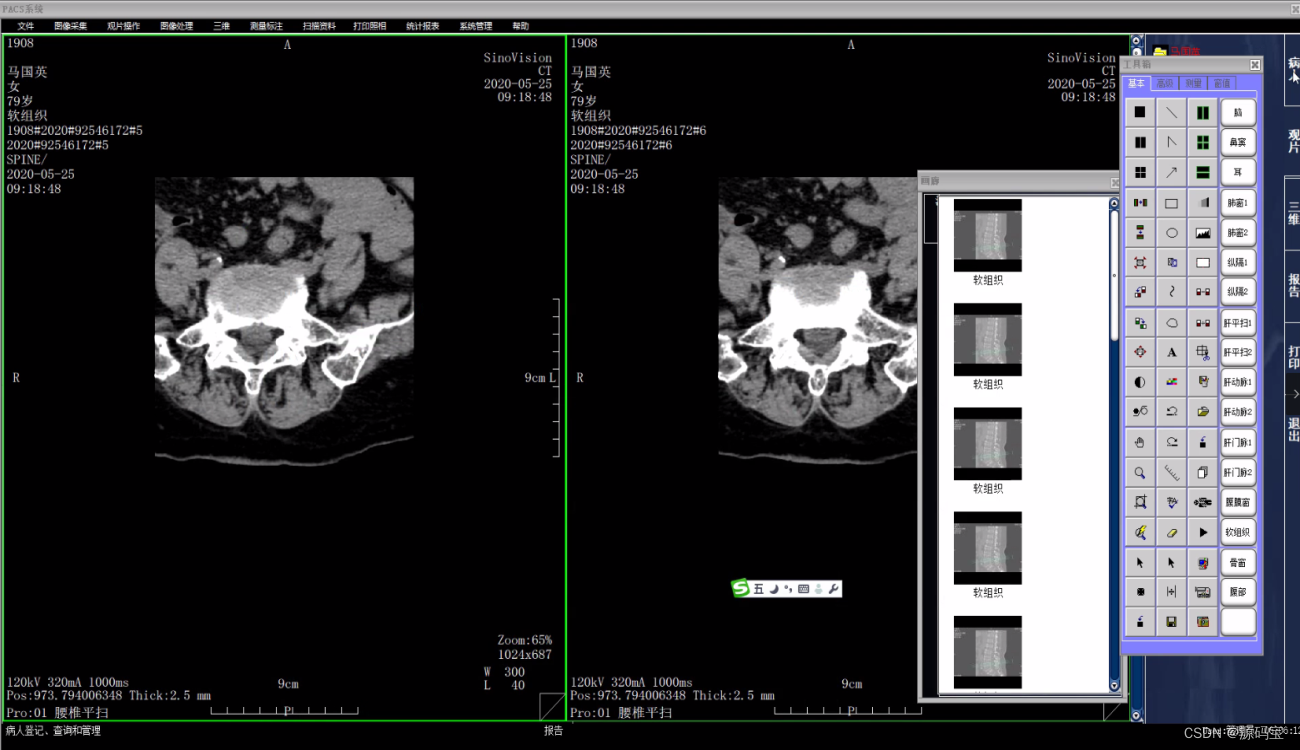

PACS系统可实现检查预约、病人信息登记、计算机阅片、电子报告书写、胶片打印、数据备份等一系列满足影像科室日常工作的功能。

全面PACS/RIS,实现对不同设备、不同图像信息的处理。

多种临床工具包,可对图像进行多种增强处理、测量、标注,充分发挥电子胶片的特点。

(5)影像处理

支持高清竖屏显示;

窗宽窗位的预设和影像上鼠标拉拖方式连续调整窗口准位;

提供定位图、定位线浏览模式;

同屏分格显示病人不同体位、不同设备的影像,供诊断比较;

影像漫游、无级缩放、局部放大;CT值坐标方式显示;

提供图像标注,角度、面积等测量,支持骨密度测量;